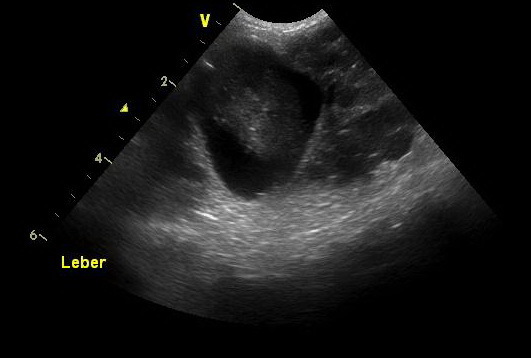

Um die Ursache zu ergründen, wurde bei Lisa eine Ultraschalluntersuchung des Bauchraumes durchgeführt. Hierzu wird der Patient mit dem Rücken in eine weiche kuhlenförmige Matte gelegt, der Bauch geschoren, mit Ultraschallgel bestrichen und mit verschiedenen Sonden „abgefahren“. Leider sind die Veränderungen, die wir im Bauchraum von Lisa finden, gar nicht schön: so ist in der Milz ein Tumor, der alsbald die Größe einer Faust hat. Darüber hinaus ist die gesamte Leber von Tumoren durchsetzt, und so kommt eine eventuelle chirurgische Hilfe für die kleine Hündin leider zu spät.